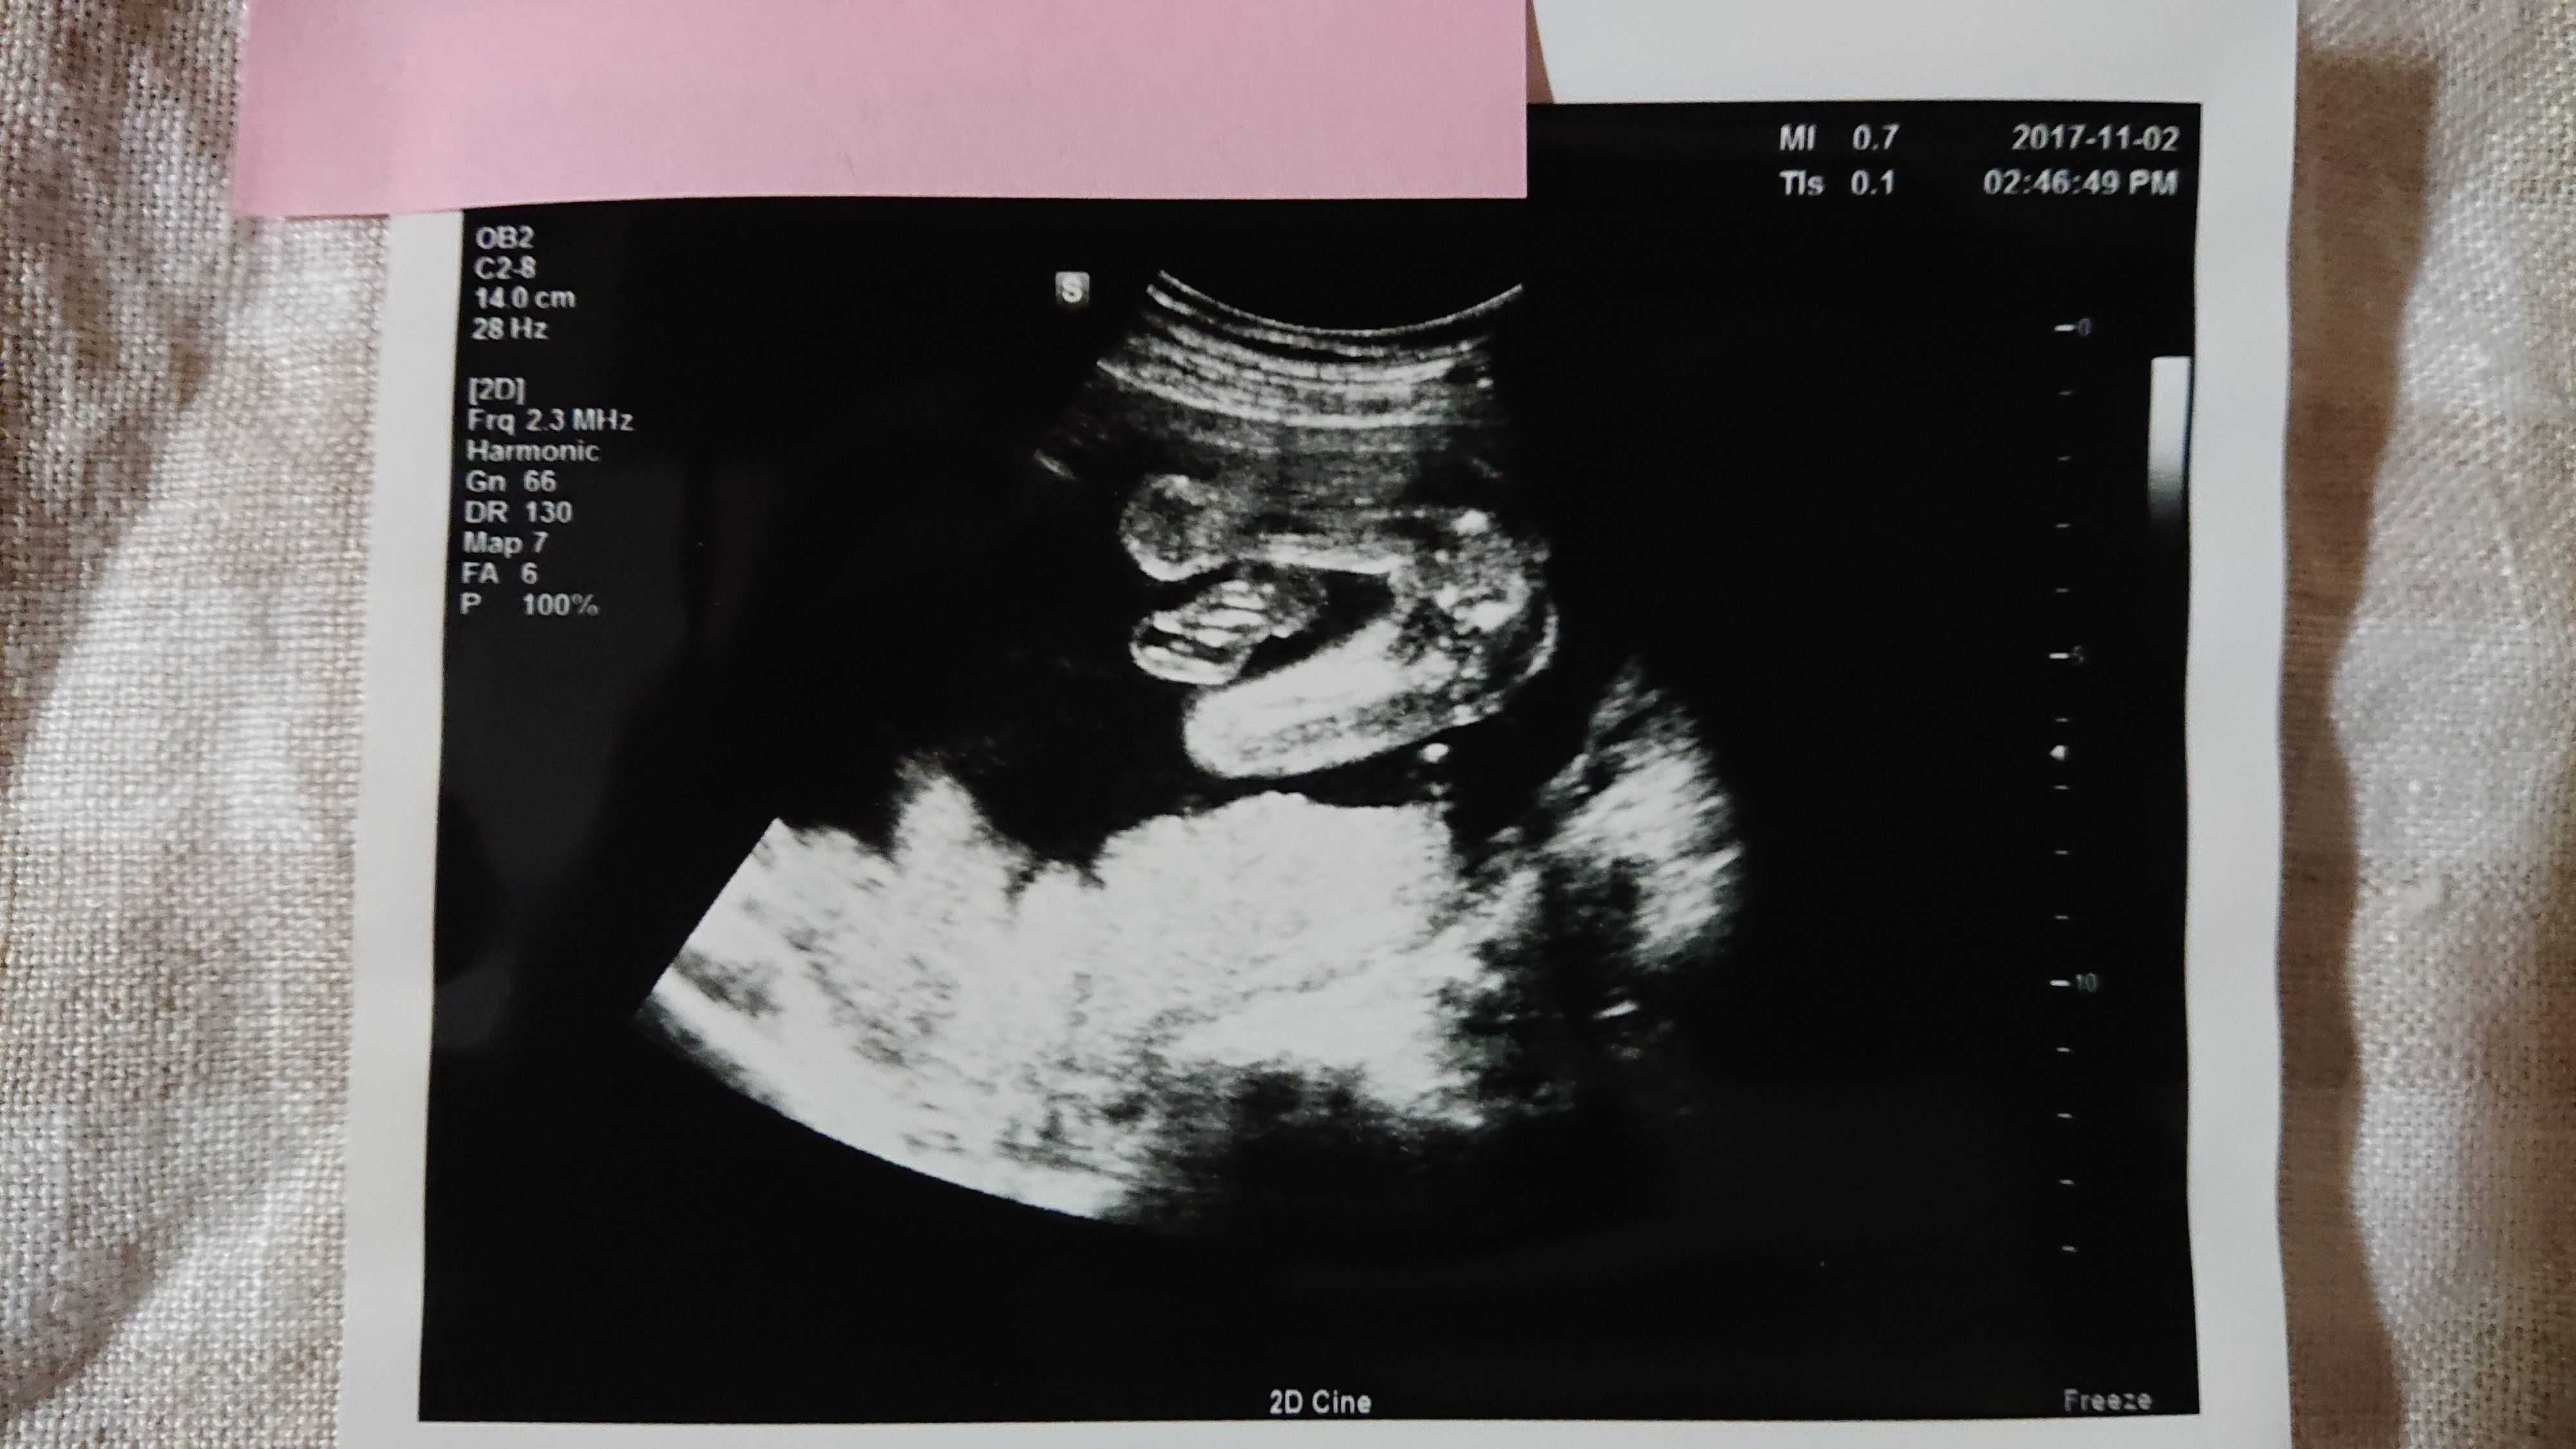

《妊娠36週目のエコー写真》

帝王切開手術の予定日から1週間前、妊娠36週目のエコー写真です。妊婦健診では「逆子が戻っていますように」と毎回願うのですが、この時も戻らず。でも、医師や看護師から「出産直前にも最終チェックするからね。その時に急に戻ってる赤ちゃんだっていたことあるから」と励まされました。切迫早産で24時間点滴が繋がっている状態では逆子体操もできないので、「戻れ~、戻れ~」と、願う事しかできませんでした。エコー写真は赤ちゃんの足です。